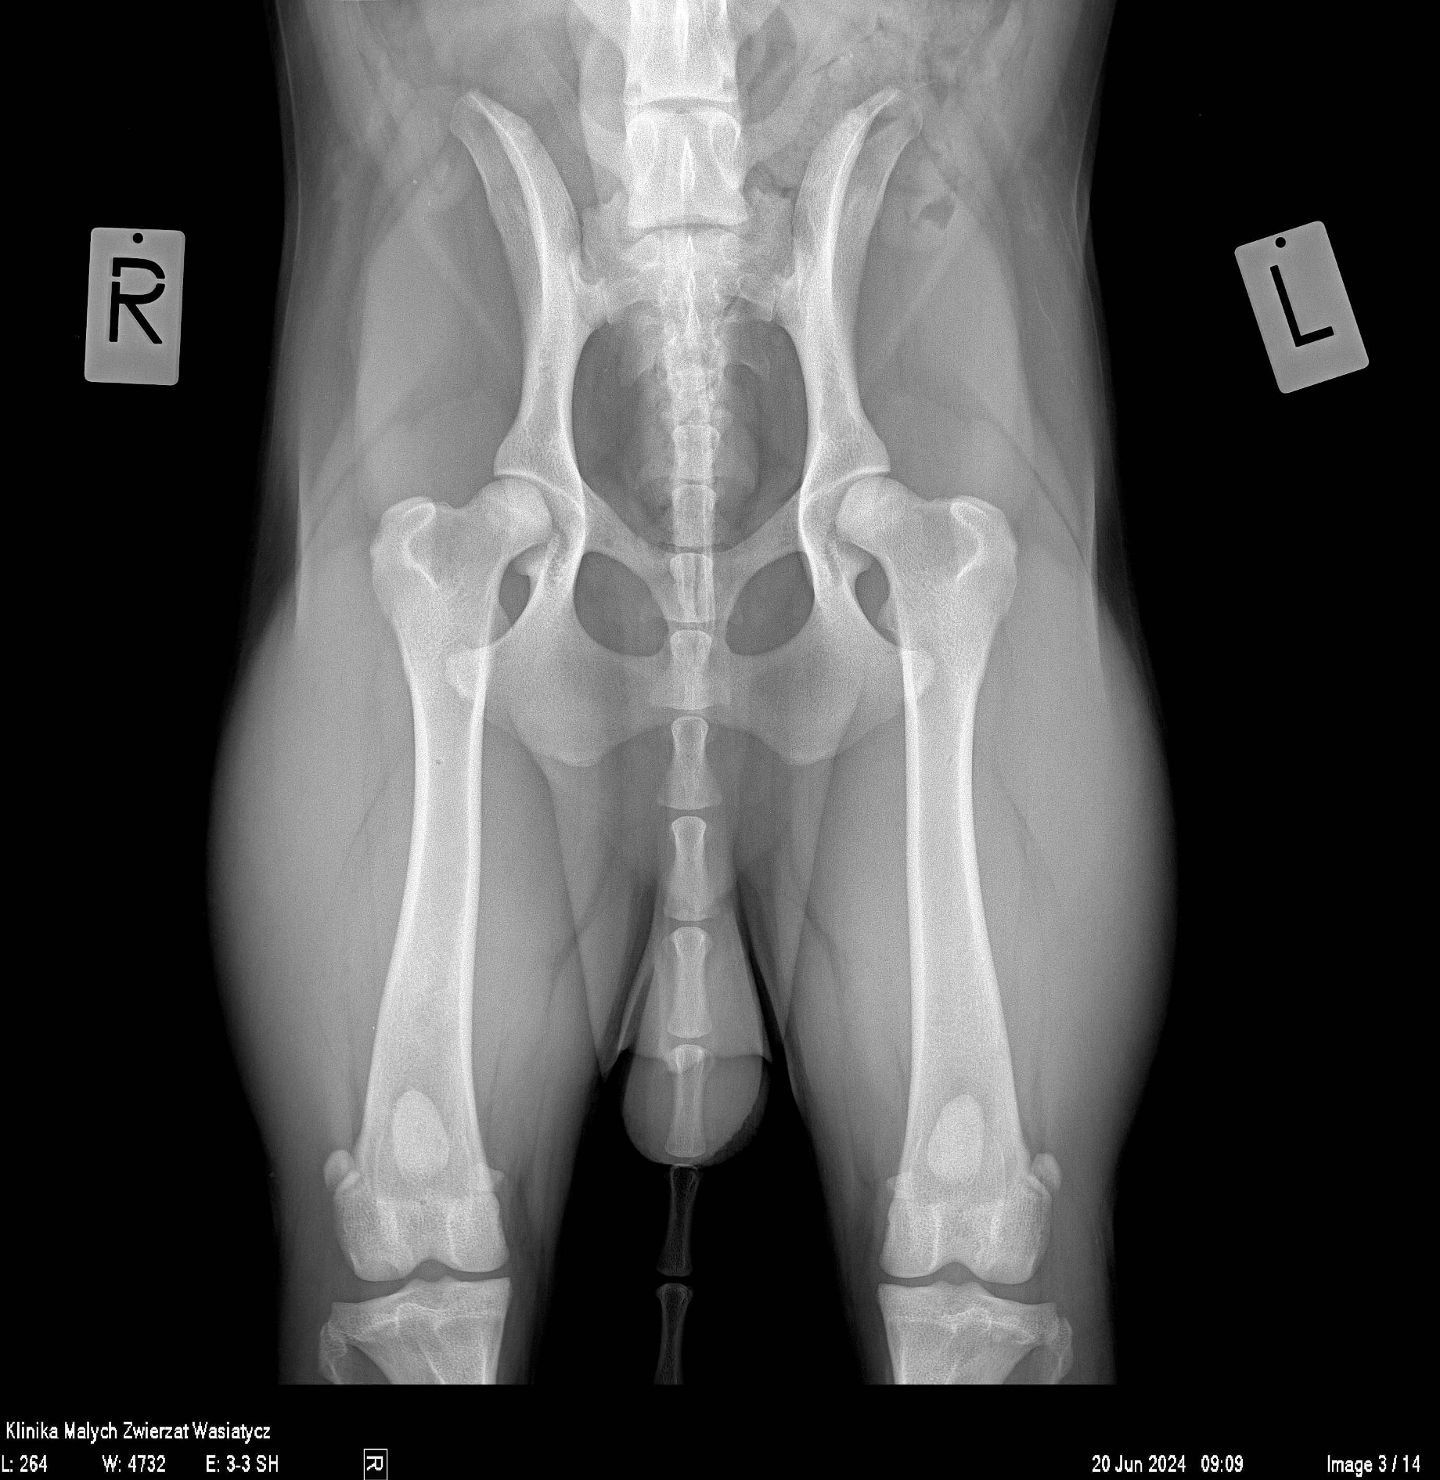

W naszej klinice pracownia rentgenowska stanowiła zawsze bardzo ważne miejsce diagnostyczne. Jako placówka specjalizująca się w ortopedii staramy się zapewnić najwyższą jakość zdjęć rtg, zarówno w zakresie dokładności ułożeń jak i parametrów ekspozycji.

Obecnie, w naszej pracy wykorzystujemy najwyższej klasy sprzęt rentgenowski hiszpańskiej firmy Initech, który został specjalnie skonfigurowany zgodnie z naszymi potrzebami. Jest to również system radiologii bezpośredniej.

Rocznie w naszej klinice wykonywanych jest prawie 20 000 zdjęć rentgenowskich. Każde z nich jest wykonywane przez stale doskonalących się specjalistów, analizowane przez wysokiej klasy lekarzy weterynarii, w tym również specjalistów radiologów. Wszystko to sprawia, że badanie rtg dostarcza maksymalną ilość informacji, która potrzebna jest w procesie diagnostycznym.